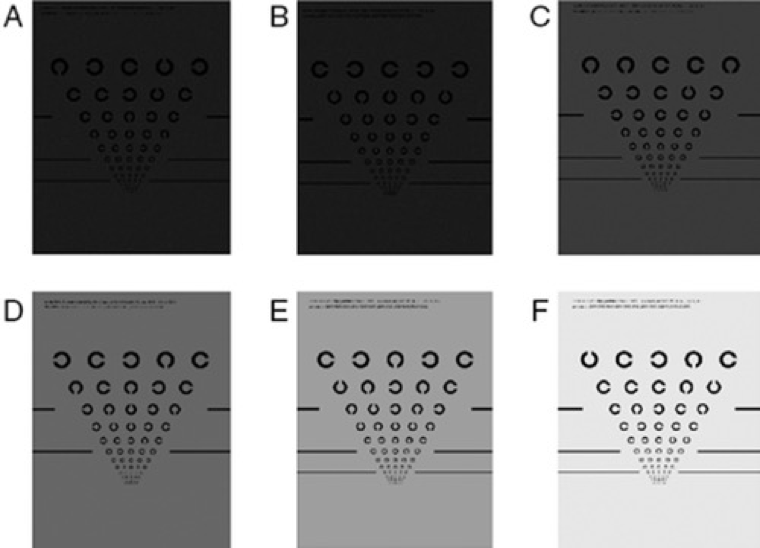

Examen de sensibilidad al contraste

El examen de sensibilidad al contraste utiliza la tabla de sensibilidad al contraste de Pelli-Robson. Esta tabla utiliza letras del mismo tamaño que progresan de alto a bajo contraste.18 Cuanto más difícil sea para una persona distinguir las letras, menor será su sensibilidad al contraste. En la DMAE, los exámenes de sensibilidad al contraste ayudan a detectar anomalías visuales que podrían no ser captadas en un examen de agudeza visual.19